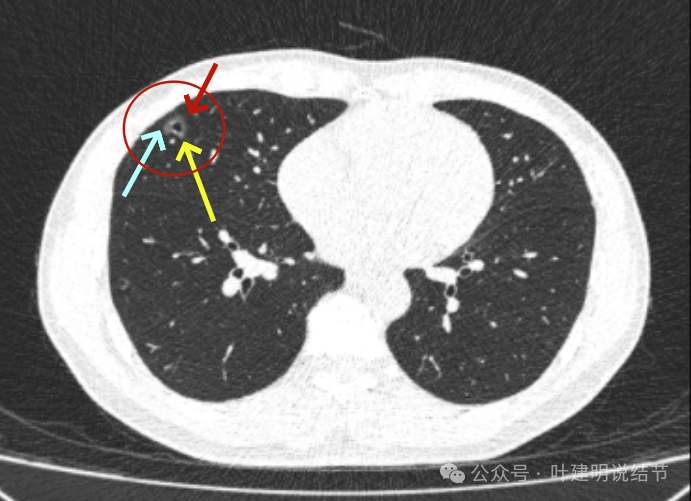

2023年10月时病灶又有进展,表面有细毛刺、灶内血管明显异常增粗,中间仍有小的空泡征,整体轮廓与边界清,大小也有所增大。磨玻璃部分的密度也较之前有所增加。

病灶出现,磨玻璃密度,轮廓较清,有微血管进入。

分叶征明显,灶内似有细支气管扩张,表面不平。

胸膜间隙征存在;血管进入与异常增粗,边缘细毛刺,整体轮廓与边界清。

中间仍有空腔征,表面细毛刺,整体轮廓清。

囊壁密度不均,有少许偏实性成分,边缘细毛刺,有小血管进入。

毛刺征明显且典型,血管进入并增粗,邻近胸膜似略有牵拉影响。

边缘部分也密度欠均匀,相应胸膜稍有牵拉影响。

表面不平,轮廓清,有分叶,有胸膜牵拉。

边缘也是磨玻璃成分,边界与轮廓清楚。